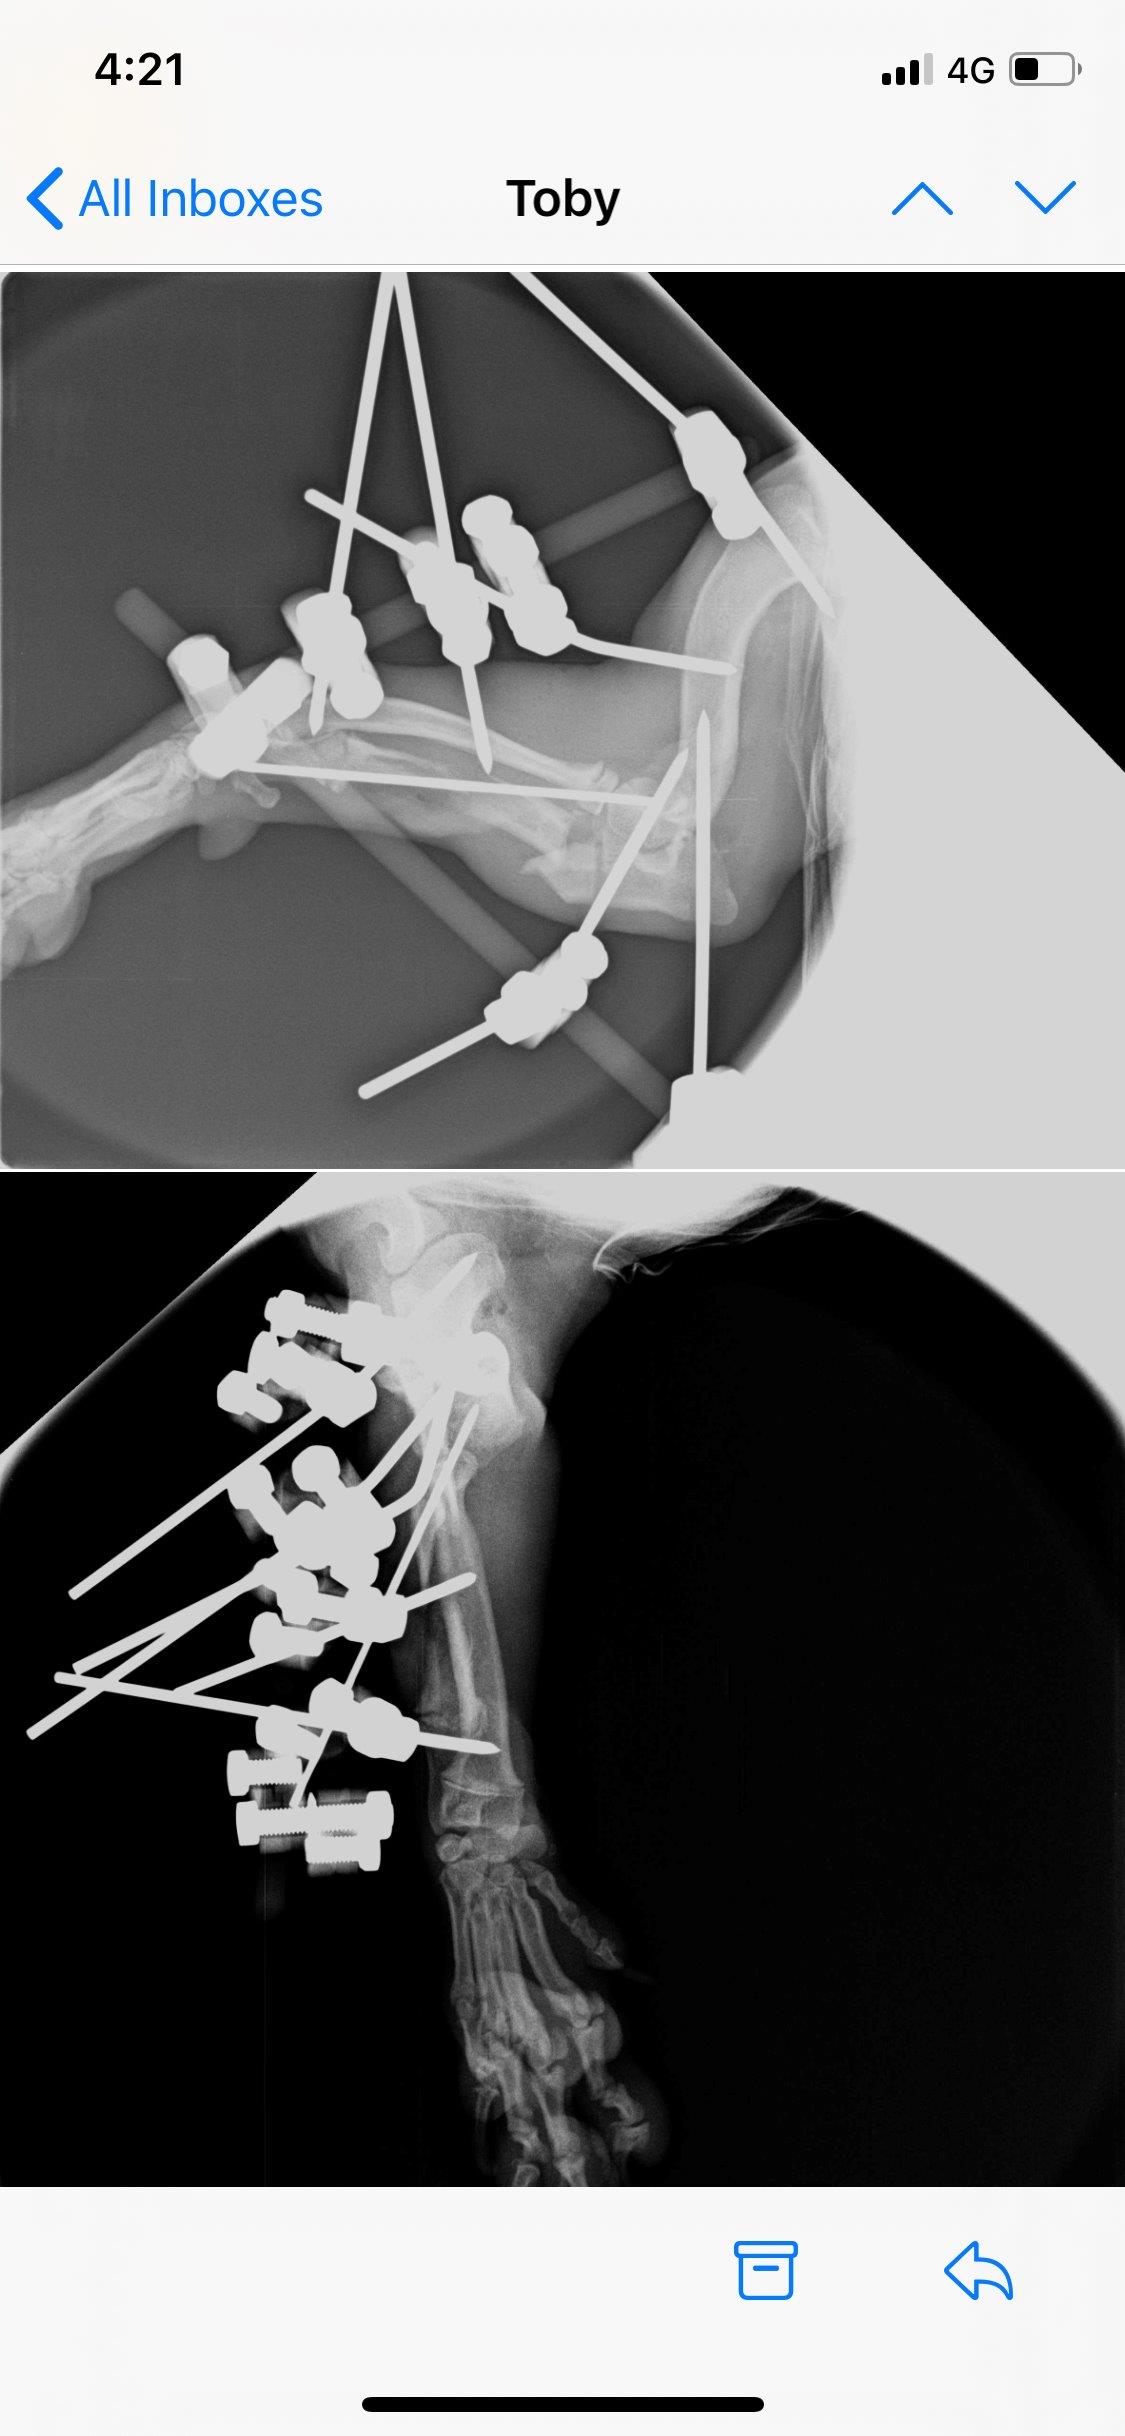

Well we are now at week 3 after Toby’s surgery. Last week after xrays it was discovered that his growth plate had cracked. So a plan was put in place to remove the pins from his leg this week. Pins came out Monday and he’s been back

At vets all day today managing the pain. The hope now is that the elbow and ulna that was rotated will stay in place with no pins in place to hold it so fingers crossed. Day one no pins and X-ray shows everything is where it should be!!! Toby has started physio and is enjoying all the massages that he is getting!!! See the new photos

Toby came through his 4.5 hour surgery on 29 October. His Ulner had to be broken in 2 places to get it aligned and then all pinned into place. See photos. He has to keep the frame on for 1 month with weekly X-rays to check it is still in place.